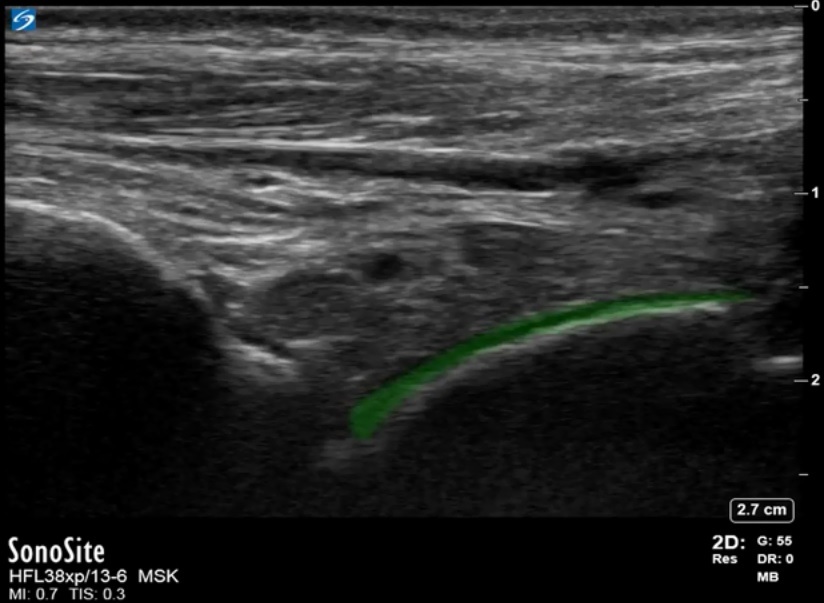

Foot & Ankle Anterior Recess Talus Image

Highlighted Area: Talus